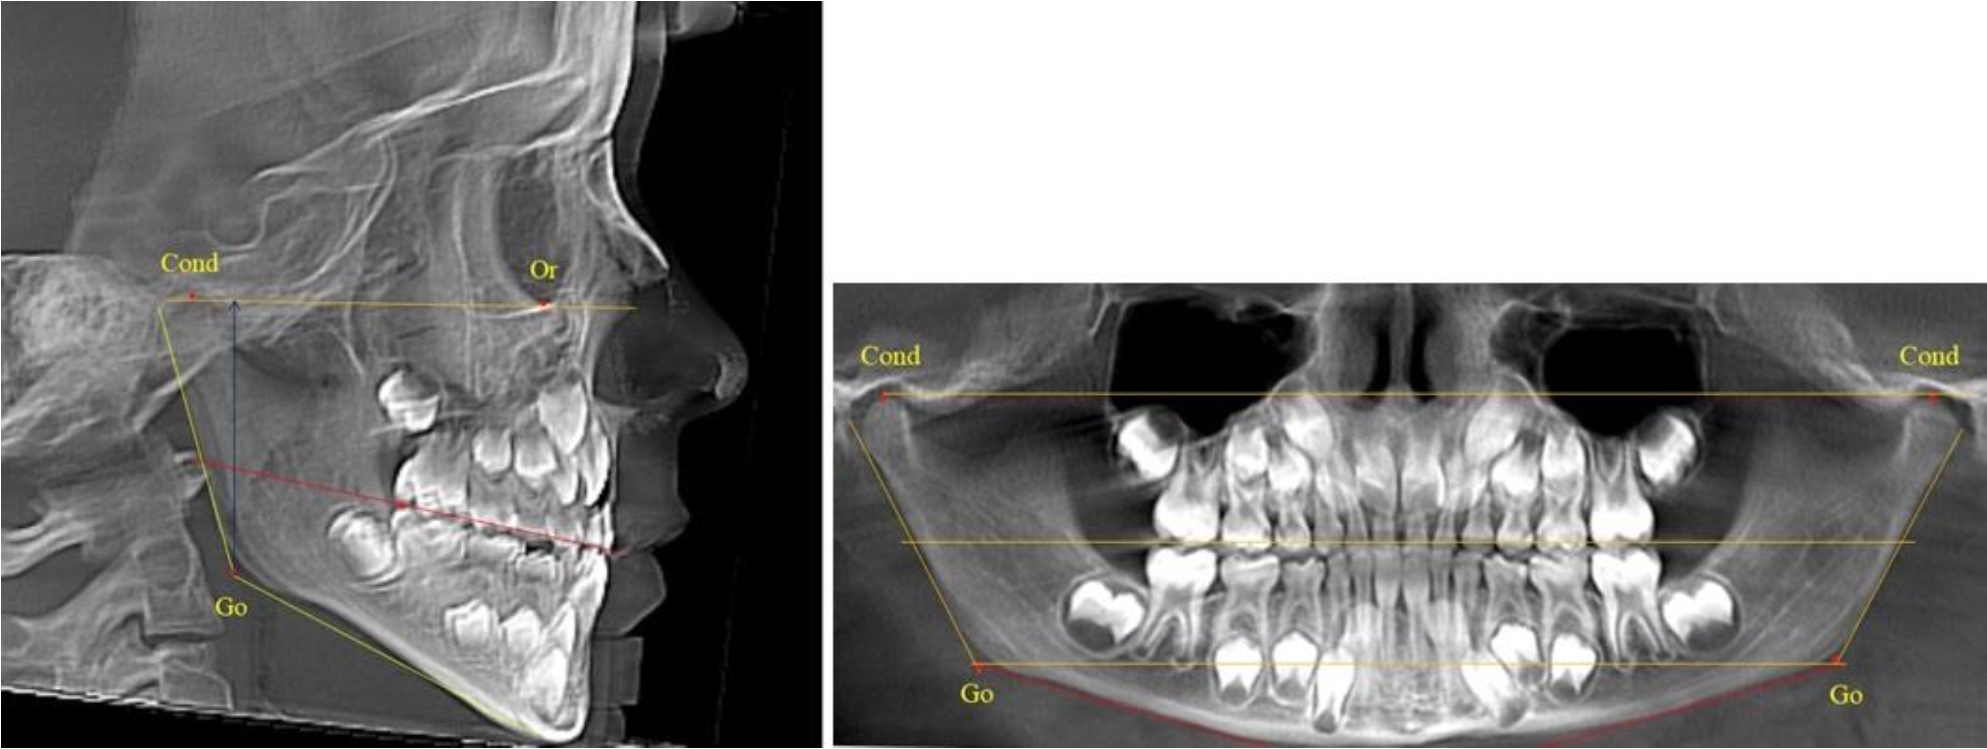

В 5-й группе были проанализированы 14 комплектов рентгенограмм, что составило (13,21 ± 3,29) % от общего числа. На всех рентгенограммах отмечен очередной этап подъема высоты прикуса, обусловленный прорезыванием вторых постоянных моляров. Окклюзионная линия делила ветвь на два отдела (рис. 5).

Рис. 5. ТРГ и ОПТГ пациента после смены молочных зубов и прорезывания вторых постоянных моляров

Высота ветви у детей 5-й группы составляла (62,87 ± 3,62) мм, что было достоверно больше, чем у детей других групп (р ˂ 0,05). При этом высота верхней окклюзионно-суставной части была (40,23 ± 2,01) мм, а нижней – (22,64 ± 1,78) мм. Высота верхней части была вдвое больше нижней, что и определяло особенности соразмерности частей ветви нижней челюсти в анализируемый возрастной период.

Относительные показатели соразмерности частей ветви нижней челюсти показали, что отношение высоты верхней части ветви к нижней в среднем составляло 1,78 ± 0,18. Отношение общей высоты ветви к верхней ее части составляло 1,56 ± 0,12, а отношение общей высоты ветви к нижней ее части было 2,78 ± 0,14, что и определяло особенности соразмерности частей ветви нижней челюсти в анализируемый возрастной период.

Таким образом, прорезывание постоянных зубов и смена молочных зубов постоянными изменяло не только высоту ветви нижней челюсти, но и изменяло соотношение ее частей, разделенных условной линией, являющейся продолжением окклюзионной линии рентгенограммы. Наиболее вариабельной структурой ветви являлась верхняя ее часть с суставным отростком. Окклюзионно-альвеолярная часть коррелировала с высотой зубочелюстных сегментов нижней челюсти.